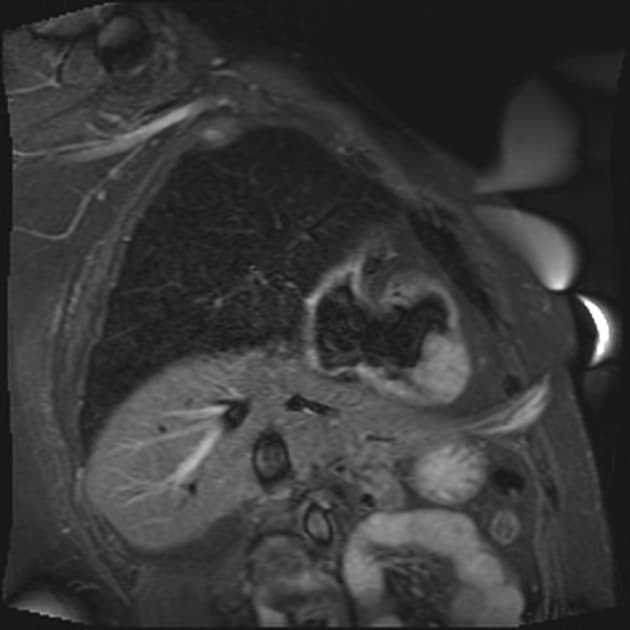

Coronal C+ arterial phase

Trong màng ngoài tim (pericardium), thấy một cấu trúc tăng tưới máu (hypervascular), đường kính tối đa 4,9 cm.

Ở trung tâm, ghi nhận các ổ vôi hóa (calcification) giảm tỷ trọng (hypodense).

Ngoài ra, tổn thương nằm giữa thân động mạch phổi (pulmonary trunk), động mạch chủ lên (ascending aorta) và tĩnh mạch phổi trái (left pulmonary vein).

Tổn thương dường như được dẫn lưu qua nhiều cấu trúc tĩnh mạch, cuối cùng đổ vào xoang vành (coronary sinus).

Không thấy rõ nguồn cấp máu động mạch.

Cũng không thấy kết nối trực tiếp với các động mạch vành (coronaries).

Một số nhánh nhỏ của động mạch vành phải (right coronary artery) có thể nuôi dưỡng tổn thương, nhưng không thấy kết nối rõ ràng nào.

So với động mạch chủ và các động mạch vành, tổn thương này có tỷ trọng thấp hơn.

Tổn thương không có biểu hiện xâm lấn.

- Tổn thương đồng nhất (homogeneous) với vôi hóa trung tâm, có hiện tượng tăng quang muộn (late enhancement), gợi ý thành phần tĩnh mạch.